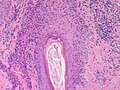

Paget's disease. H&E stain. | |

| LM | large epithelioid cells - nested or single - in the epidermis, clear/pale cytoplasm (occasionally eosinophilic), large nucleoli |

Features:[2]

- Epitheliod morphology (round/ovoid).

- Cells nested or single.

- Clear/pale cytoplasm key feature - may also be eosinophilic.

- Large nucleoli.